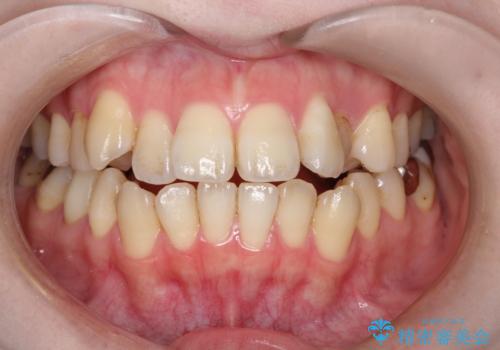

[ セラミック治療 ] 前歯の見た目を改善したい

担当医 大元洋佑